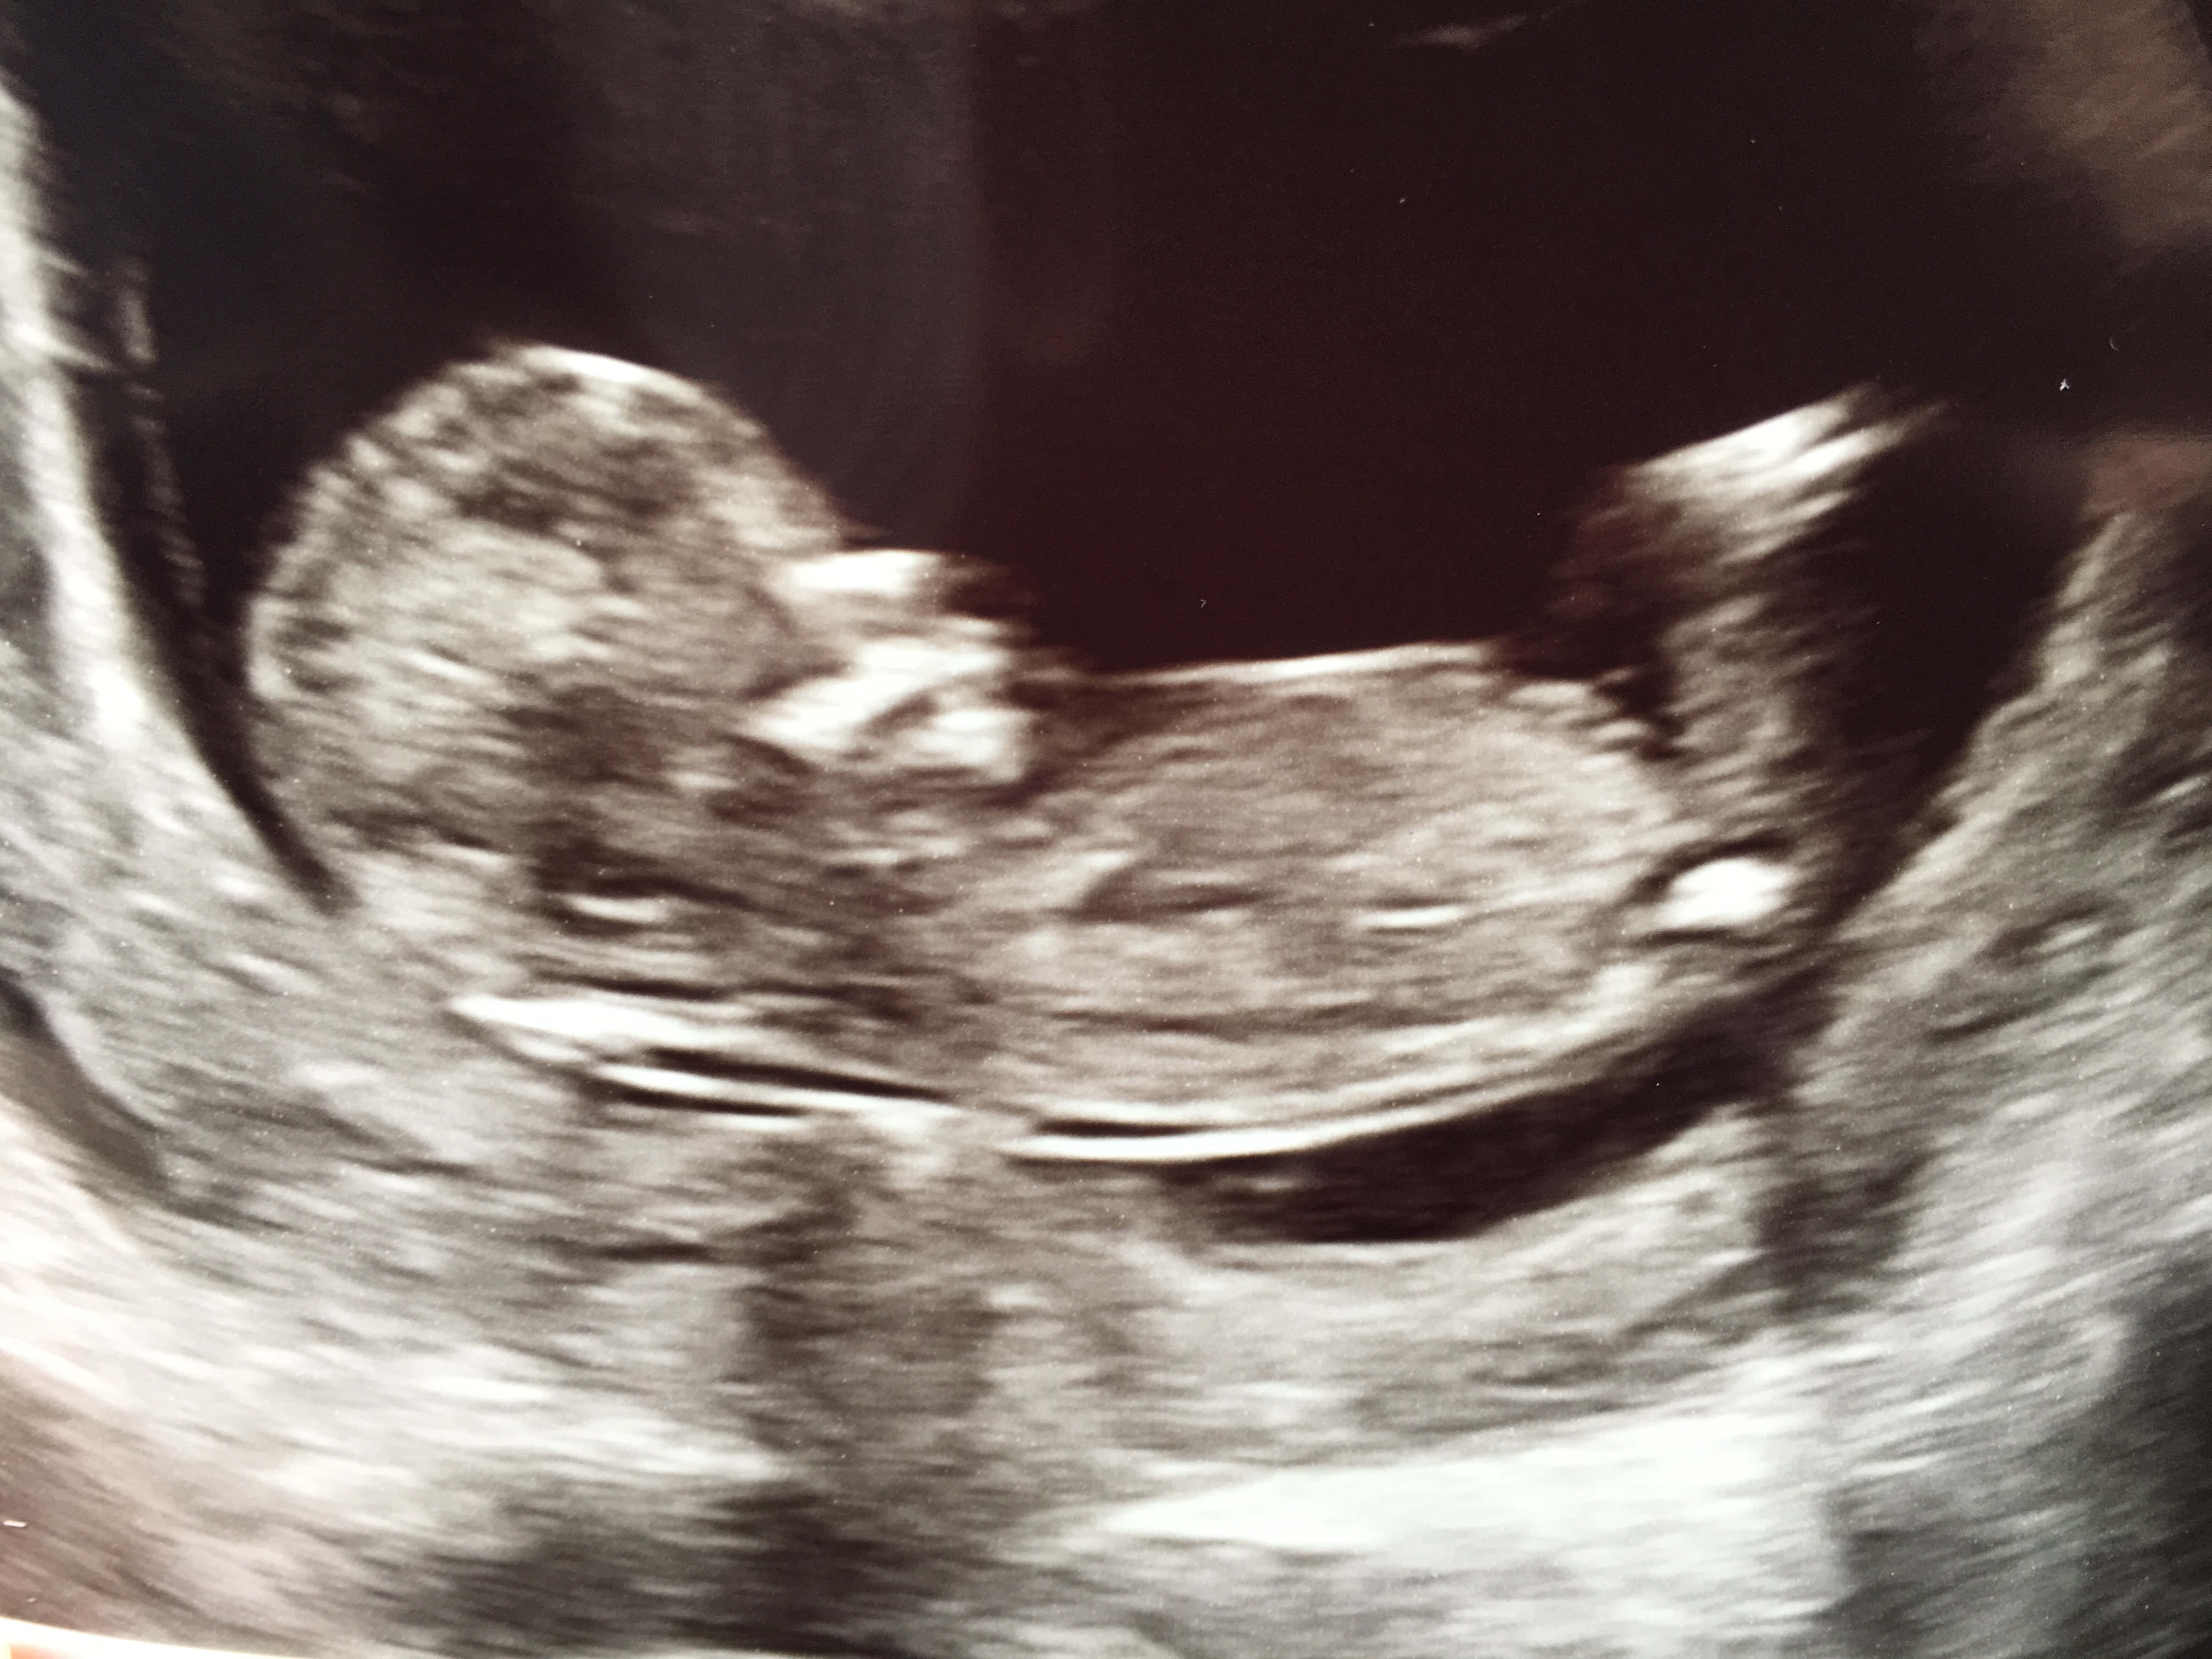

I’ll post my other pictures too in case that helps it look more clear!

That is a really tricky one! In one picture I would have said girly

But on another one I can see some stacking on the nub so would indicate a boy

Looks like it's 50/50 still!!